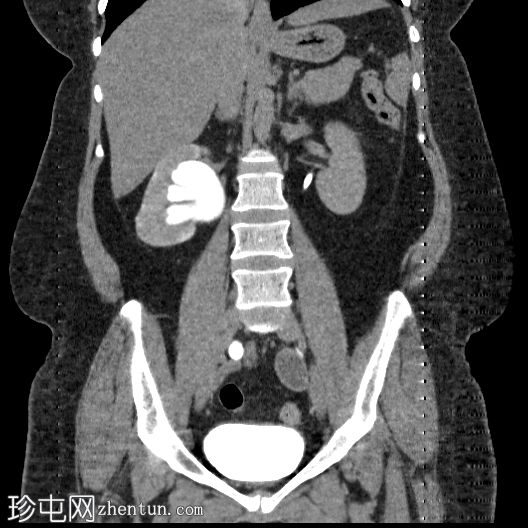

冠状位肾排泄期

右肾中度肾积水,输尿管积水延伸至S4椎体水平。延迟期图像显示阴道残端扩张并充满造影剂,与右侧远端输尿管相通。

平扫图像显示左侧肾盏系统内有残留造影剂。

延迟期图像显示右侧肾盂呈斑片状强化,提示延迟性肾图,可能由远端梗阻引起。